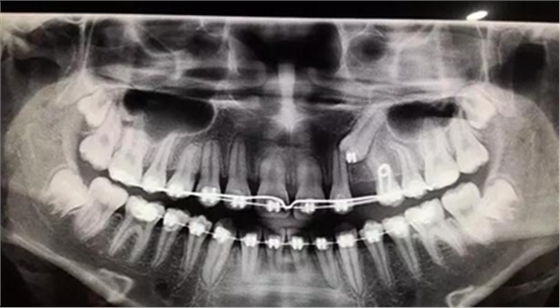

全景片